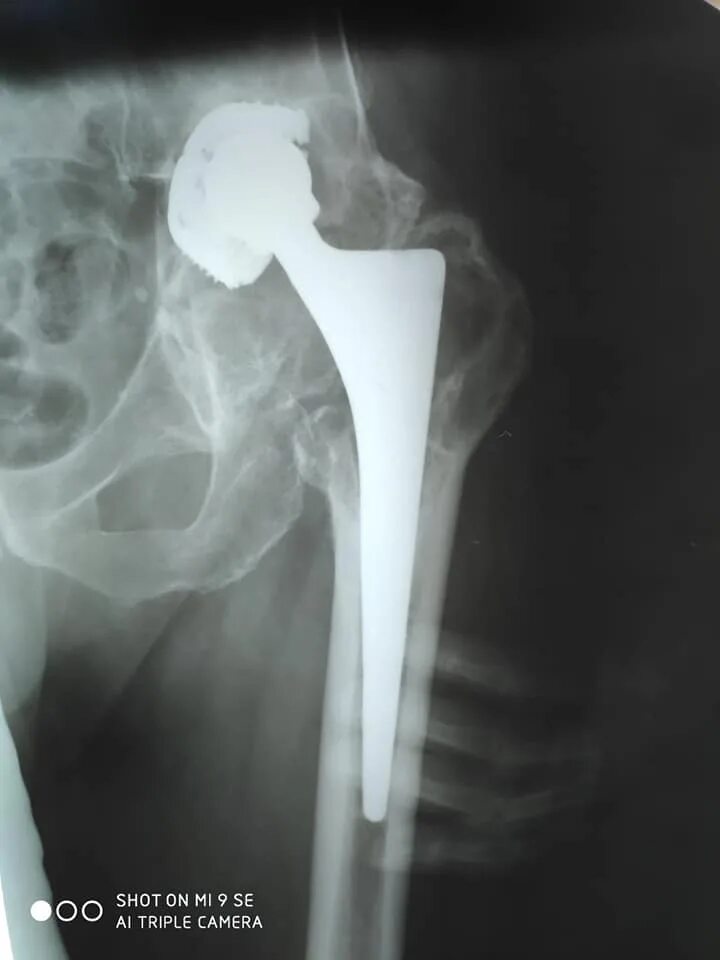

Что такое коксартроз тазобедренного сустава 2 степени